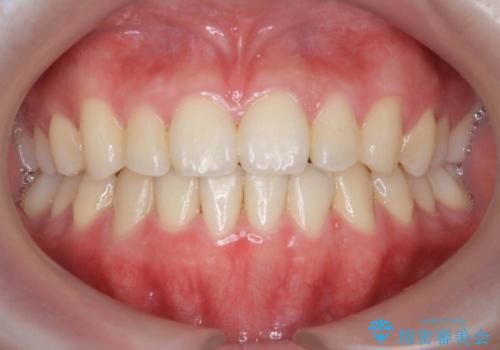

[ マウスピース矯正 ] 前歯のねじれを治したい

![[ マウスピース矯正 ] 前歯のねじれを治したいの症例 治療後](https://seimitsushinbi.jp/wp/wp-content/uploads/2022/01/IMG_0069-500x350.jpg?v=1641870943)